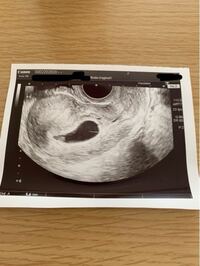

知り合いからエコー写真を見て首後ろ等の空間がダウン症のような、、、といわれました。 12週4日です。 エコー写真こんな感じだったけど ダウン症じゃなかったよ!てゆー方と買いますか? 医師からは何もダウン症なエコー写真ではダウン症かどうか100%判断できません。 しかし、ダウン症の可能性があるかは判断できます。 不安になる必要はありませんが、「もしかしたらそうなのかも」と心構えがしやすくなりますよね。 ダウン症の可能性はエコー写真からわかる!1/11/21 · ダウン症の胎児は首の後ろに厚みがあります。 こちらのエコー画像例の様に、ニコ君にも首の後ろに厚みがありました。 ただ、これも現地の医師によれば問題無しと判断されました。 妊娠7ヶ月からダウン症がエコーで分かるのか? 妊娠11週からダウン症はエコーで分かる可能性がある!

ダウン症エコー写真 週目によるbpd Nt Flを解説 ダウン症ステーション5/12/09 · 性別がわかる方、教えていただきたいです。 週の赤ちゃんの横向きのエコー写 5 ダウン症のエコー写真について ダウン症の子は首の後ろにコブがあるとかむくんでいるとか言いますがこの写 6 妊娠23週目初めての赤ちゃんです。エコー検査で、赤ちゃんの8/31/17 · ダウン症の子のエコー写真の特徴を教えてください。。 今日、検診に行きました心臓の動きなど、色々見てもらって特に異常はない順調ですねと言われて安心しましたが、家帰ってじっくりエコー写真を見てると、首から頭らへんに浮腫というか、隙間があった気がして。。 はじめまして

このエコー写真からダウン症に見られる首の浮腫あるようにみえる Yahoo 知恵袋